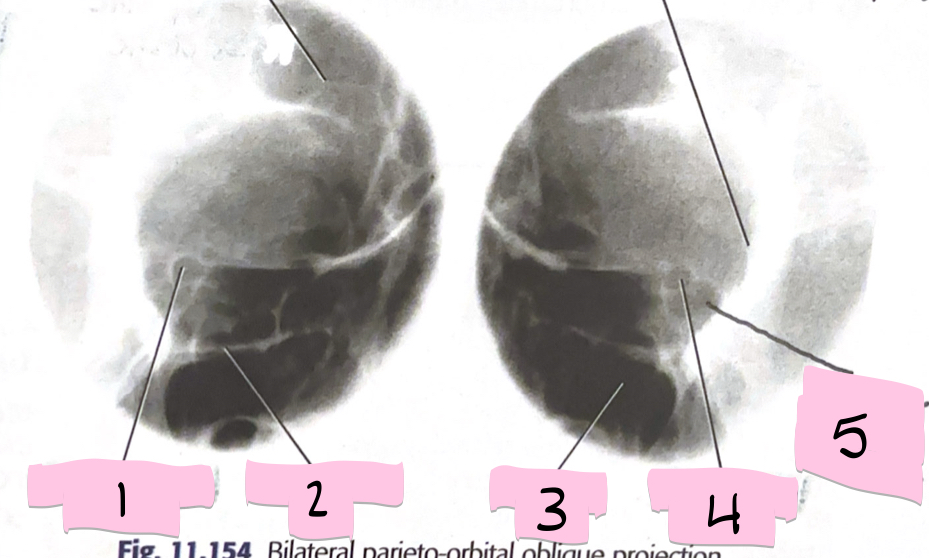

What is 1 pointing to?

Optical foramen and canal

What is 2 pointing to?

Inferior orbital rim

What is 3 pointing to?

Maxillary sinus

What is 4 pointing to?

Optic foramen and canal

What is 5 pointing to?

Superior orbital fissure